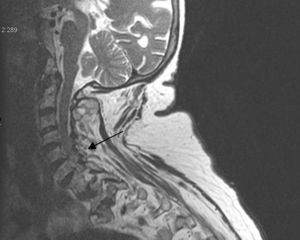

Presentamos el caso de una mujer de 82 años que consulta por dolor cervical intenso, mal controlado con analgésicos. Como antecedentes de interés destaca la presencia de una fibrilación articular anticoagulada, espondiloartrosis y condrocalcinosis radiológica en rodillas. En la exploración realizada destaca un dolor espontáneo en la región cervical, irradiado a la región occipital y mastoidea, con rigidez y bloqueo doloroso a la movilización del cuello y sin alteraciones neurológicas.

En los estudios radiológicos realizados destaca la aparición de una espondiloartrosis cervical y calcificaciones en el ligamento transverso del atlas y ligamentos alares a nivel de la articulación atlo-axoidea (fig. 4).